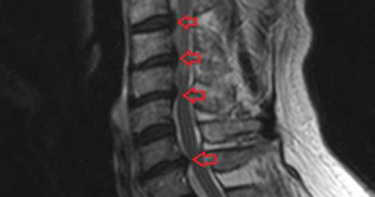

若出現腳麻、手麻等問題,許多人會覺得是循環不好造成的。不過,國泰綜合醫院神經外科總住院醫師王祺、國泰綜合醫院顧問醫師黃金山表示,腳麻、手麻也有可能是頸椎椎間盤突出衍生的症狀。頸椎椎間盤突出壓迫 出現手麻、腳麻等症狀頸椎椎間盤突出(Cervical Spinal Disc Herniation)會導致頸部神經受到壓迫,產生疼痛、肌肉功能障礙等問題。王祺醫師指出,頸椎椎間盤突出最常見的症狀為頸部疼痛,並會蔓延至肩膀、手臂、手指產生麻木、刺痛感。許多病人常會抱怨手麻、刺痛。此外,黃金山醫師表示,頸椎椎間盤突出也有可能導致頭痛等問題,嚴重甚至會造成脊髓壓迫、損傷,導致病人產生腳麻、走路不穩的情形。年齡、遺傳會增加疾病風險 低頭族也須注意有些人會因為先天生性椎管狹窄而產生頸椎椎間盤突出的問題,但其實椎間盤也會因為年齡增長,水份減少、彈性漸漸降低,而更容易產生頸椎椎間盤突出的問題。此外,黃金山醫師提到,像是外傷、關節炎、骨質疏鬆等,也都有可能會增加椎間盤突出壓迫脊隨的風險。不過,王祺醫師也特別提醒,雖然頸椎椎間盤突出的原因與年齡增長、遺傳等因素有關,但是現在手機、3C產品等越來越普遍,許多人成為「低頭族」,或是因為工作的關係需要長時間盯著螢幕、久坐,再加上姿勢不良、肌肉力量不足等情況,這也讓越來越多人有頸椎椎間盤突出的問題。改變生活習慣 找出適合的治療方式目前,頸椎椎間盤突出的治療方法,包含物理治療、藥物、手術等,也可透過按摩、針灸等治療。黃金山醫師表示,治療方式其實有很多種,不過如果症狀較輕,通常會建議先改變生活方式,並使用藥物來緩解病情。像是調整不良坐姿、避免長時間低頭滑手機或坐在電腦前,並練習拉伸頸部、鍛煉肌肉,以及使用抗發炎藥物、止痛藥等緩解症狀。但若是症狀嚴重,出現走路不穩、脊髓病變等,或是嚴重肩頸疼痛無力等影響生活品質時,可能就需要手術治療。手術的方式有椎間盤切除術和人工椎間盤置換術等。王祺醫師提到,針對嚴重的椎管狹窄病人還需合併椎板整形術,來擴大神經管空間。不過,王祺醫師、黃金山醫師強調,每個人的狀況不同,建議民眾如果有相關症狀還是前往醫療院所就醫,經過醫師檢查、診斷,找出病因後再針對各別情況,討論出最適合自己的治療方式。

隨著「低頭族」愈來愈多,脖子長時間姿勢不良,頸椎間盤突出有年輕化趨勢。初期可用藥物及復健治療,約有一成病人因嚴重壓迫神經需動手術。40多歲的王小姐從事秘書工作多年,長時間使用電腦,出現肩頸痠痛、手麻無力的情形,原以為是肌肉緊繃疲勞,照了X光竟是頸椎間盤突出,壓迫到頸部神經,還好發現得早,在藥物及復健治療下,逐漸改善症狀。臺北市立聯合醫院和平婦幼院區神經外科主治醫師莊淵丞說明,人體頸椎共有7節,每節之間有一個軟骨稱為「頸椎間盤」,具有支撐與緩衝作用,讓關節得以前後左右靈活轉動。由於頸椎的前方是食道,兩側為頸部大血管,後方為頸椎神經,一旦頸椎間盤突出,可能會壓迫到周遭的神經或血管,產生相關症狀,又以神經壓迫較為常見。如果壓迫到較高位置(第1、2條頸神經),會引發後頭部或後頸部疼痛,因此,有些病人會誤以為是頭痛問題;如果壓迫到中低位置的頸神經,則可能影響肩頸到手部的功能,出現痠麻疼痛的感覺。頸椎間盤突出屬於退化性疾病,主要是因長期維持不良姿勢所引起,常與職業相關,例如從事文書處理、司機,容易不自覺地脖子前傾打電腦或開車,隨著年齡增長,發生機率愈高。然而,隨著滑手機的低頭族變多,愈來愈多年輕人有這方面困擾。此外,需要長時間戴很重的頭盔,像是軍人、美式足球員等;還有外力撞擊,如車禍、運動傷害等,也會導致頸椎間盤突出。頸椎間盤突出初期建議以消炎止痛藥緩解不適,搭配復健並且多休息,通常可獲改善,僅約一成左右的病人因嚴重壓迫到神經,甚至造成交感神經問題,才需要手術。莊淵丞指出,現在頸椎間盤手術已相當進步,採微創方式,傷口很小,少有併發症。通常會先清除突出的頸椎間盤,再置換人工支架。健保給付的傳統支架為固定式,術後頭頸轉動角度會變小,如果只更換一兩節,影響程度並不明顯。而新式的人工關節,可保留關節活動功能,屬自付項目,病人可依需求選擇。無論選擇哪一種,術後都應配戴護頸約1至3個月時間,後續追蹤確認人工支架或關節沒有移位,復原情況良好,方可移除護頸。莊淵丞提醒,過去頸椎間盤突出多半是職業傷害,現在低頭族增多,有年輕化趨勢。建議看手機時要擺在視線正前方,避免低頭使用,像搭捷運時人手一機低頭猛滑,即使只有10分鐘,長期下來對頸部的傷害也不小。平日需有適當休息與活動,抽空舒展一下頸肩肌肉,一旦有不適症狀,應盡早就醫。